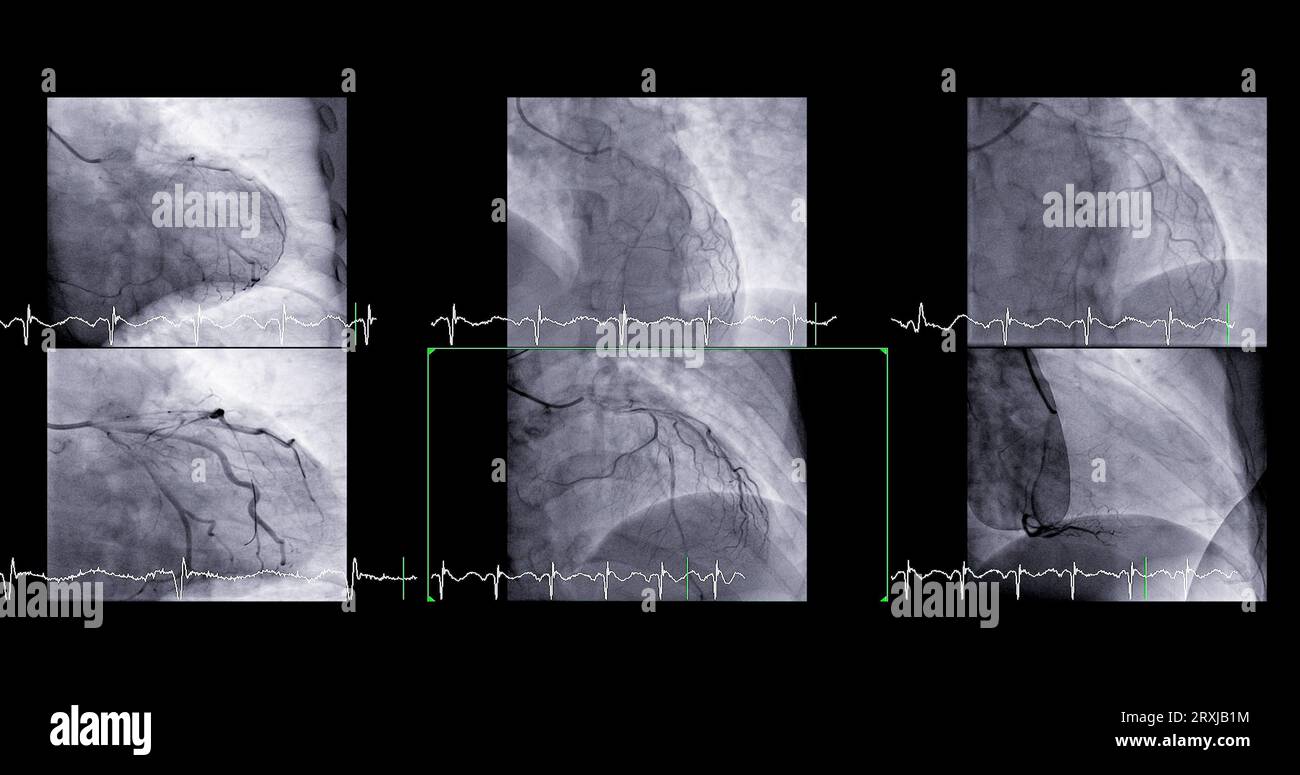

Left heart catheterization RAO cranial view showing left main coronary

Left heart catheterization RAO cranial view showing left main coronary Can A Heart Catheterization Cause A Heart Attack Doctors can use cardiac catheterization to detect heart valve disease, such as valve stenosis (narrowing). I recently had a heart attack, but a cardiac catheterization found no blocked arteries. Yes, this type of heart attack is called a myocardial infarction in the. Cardiac catheterization (also called cardiac cath or coronary angiogram) is an invasive imaging procedure that allows your healthcare. Can A Heart Catheterization Cause A Heart Attack.

Left heart catheterization (left coronary angiography) Angiographically Can A Heart Catheterization Cause A Heart Attack Major complications are very rare. What are the risks of cardiac catheterization? During cardiac catheterization, a medical team led by an “interventional” cardiologist guides a narrow tube from your wrist or thigh into your heart, giving them access to. Cardiac catheterization (also called cardiac cath or coronary angiogram) is an invasive imaging procedure that allows your healthcare provider. Doctors can. Can A Heart Catheterization Cause A Heart Attack.